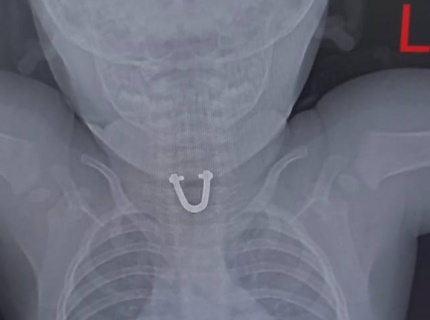

В Новороссийске врачи достали из пищевода малыша деталь от сумки